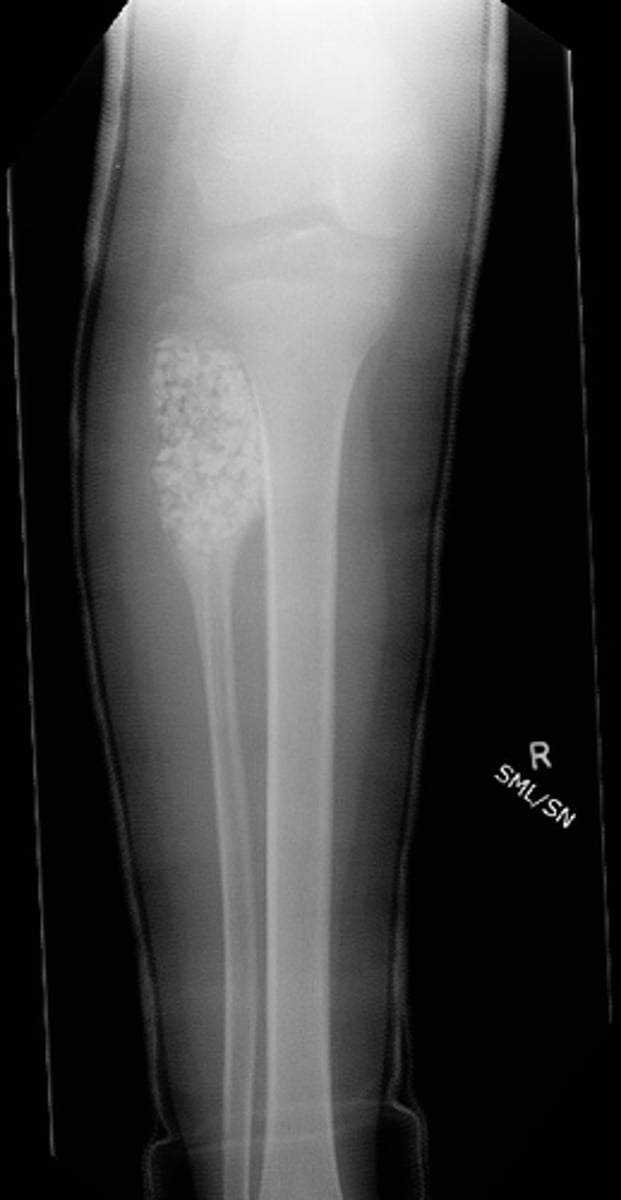

Lateral proximal tibia

Bone

<p>Bone</p>

- Longitudinal: epiphysis/metaphysis (up to joint surface)

- Eccentricity: eccentric

- Transverse: medullary

Location

<p>Location</p>

Monostotic

Mono/polyostotic

<p>Mono/polyostotic</p>

New cards

>1 cm

Size

<p>Size</p>

- Lytic

- Geographic

- Short zone of transition

Behavior

<p>Behavior</p>

Cortex

<p>Cortex</p>

Giant cell tumor

Most likely diagnosis?

<p>Most likely diagnosis?</p>

Refer to orthopedist or oncologist

Next step?

<p>Next step?</p>

Could be aggressive (20%)

Concerns/complications?

<p>Concerns/complications?</p>